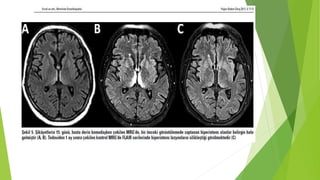

Wernicke ensefalopatisi

 3.ve 4. ventrikül çevresindeki diensefalik ve mezensefalik disfonksiyon

 Thiamin eksikliği, YB hastalarında az tanı alıyor

 Literatur bilgileri vakaların ancak %20’sinin tanınabildiğini, çoğunun gozden kactığını

gostermektedir

 Parenteral N , GIS cerrahisi sonrası, hemodializ , ileri kanser hastaları

 Triad: ataxi, konfuzyon, oftalmopleji

 Oküler: horizontal nistagmus, bilateral abdusens paralizi, oftalmopleji, pupiller anormallik

 Apati, dikkat bozulması,yorgunluk

 Ataxi: vestibuler ve serebellar disfonksiyon

 Hipotermi ve hipotansiyon: hipotalamik disregülasyon

 IV thiamin tedavisi, oküler belirtiler en hızlı iyileşir, ataxi ve EP günler ve / veya haftalar

sonra iyileşir, hafıza ve bilinç bozukluğu kalıcı olabilir